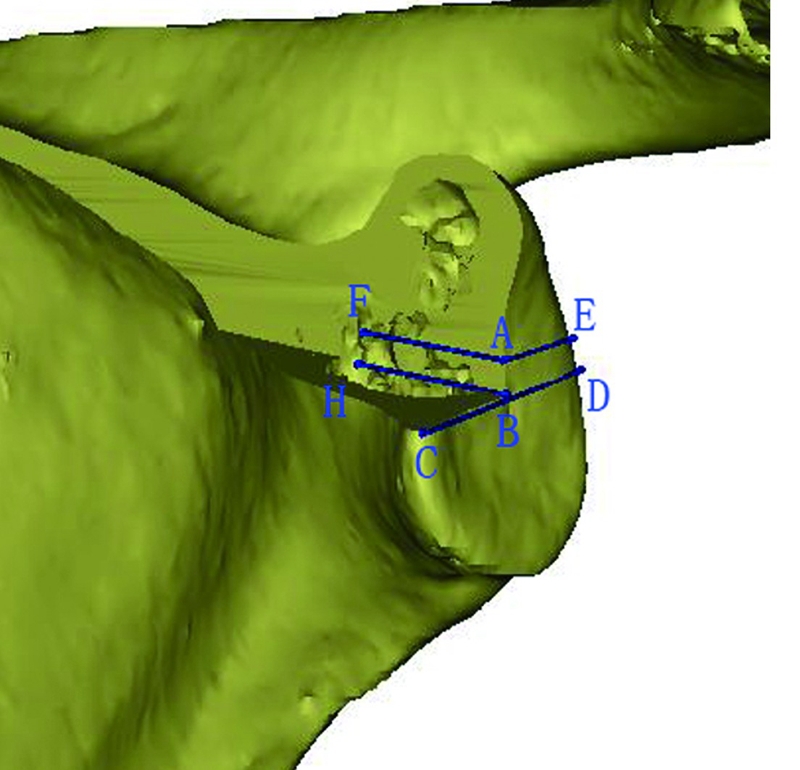

Codsi等将61个肩胛骨样本进行CT扫描并进行三维重建,依据肩胛盂上下径将其分为6组,获取不同分组肩胛盂体部前后壁骨内边界,描绘出不同分组肩胛盂体部三维形态;依据肩胛盂上下径将不同分组的肩胛盂体部三维结构缩放为常规大小对三维形态进行比较,发现在所研究正常人群中,肩胛盂体部内部三维结构一致。肩胛盂体部内部形态的统一性,可指导关节假体设计、重建,帮助理解肩关节发育不良及关节退变性疾病的发生,但Codsi等对肩胛盂穹隆的三维结构并没有定量研究,临床应用有一定的局限性。Bicknell等对72个肩胛骨标本行CT扫描,测量了肩胛盂中心前后径、上下径,认为肩胛盂穹隆内部结构相对一致,冠状面为矩形、水平面为三 角形的假体更符合肩胛盂体部的解剖学形态。肩胛盂体 部男性解剖学参数较女性大,存在显著的性别差异,但肩胛盂体部内部形态男女未见差异。除此之外,Bicknell等还测量了肩胛盂中心的上下径、前后径等解剖学参数; 但是肩胛盂体部解剖结构复杂,单以中心测量很难反映其总体解剖学形态。Keisuke等应用三维重建技术重建肩胛盂体部的三维解剖,进行定量分析,测量了以肩 胛盂中心22×12mm范围内间隔2mm的肩胛盂体部深度和肩胛盂中心上下 4mm肩胛盂体部的前后径,使局部复杂的结构可视化、定量化,并对反肩置换假体设计提供参考(图7) 。

图7 肩胛盂体部深度、前后径的测量示意图。应用CT数据对肩胛骨进行三维重建(移除了肩胛盂体部前上部分) ,以肩胛盂上下极、前后缘的连线建立坐标系,测量肩胛盂体部深度和肩胛盂体部前后部宽度。图中线段AF、BH为肩胛盂中心和其上2mm肩胛盂体部深度;线段BC为肩胛盂体部前部宽度;线段AE、BD为肩胛盂体部后部宽度。线段AE、BD之间的距离为2mm,可对肩胛盂体部形态进行定量化分析